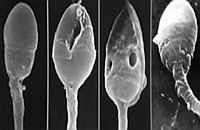

Морфология сперматозоидов считается очень важным показателем спермограммы. Данный показатель спермограммы отражает процентное содержание способных к оплодотворению сперматозоидов. Некроспермия – снижение концентрации живых сперматозоидов. Агглютинация (склеивание сперматозоидов) может наблюдаться при хронических воспалительных процессах в мужских половых железах. При агглютинации подвижность сперматозоидов почти всегда снижается.